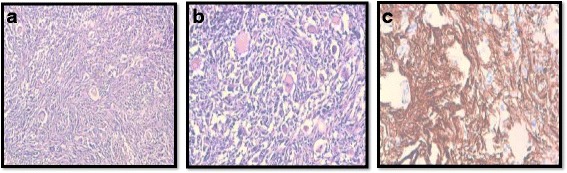

A 10-year-old white girl, presented with a 10-month history of convulsive seizures without signs of intracranial hypertension. A computed tomography (CT) scan revealed a voluminous mass in her perilateral ventricle with similar attenuation to that of cortical gray matter (Fig. 1a), following administration of a contrast product, the mass showed marked enhancement (Fig. 1b). Surgery was performed with complete resection of the tumor. An extemporaneous examination was in favor of a benign ganglioglioma tumor. After fixation in 10 % neutral-buffered formalin, embedding in paraffin and staining with hematoxylin, eosin and safran, histologically the tumor was found to be composed of fibrillated spindle cells and globular large cells, with abundant eosinophilic cytoplasm, and voluminous, eccentric nucleus, and large nucleoli, producing an aspect of ganglion cells; mitosis, necrosis, and microvascular proliferation were not rated (Figs. 2a and 2b). Calcifications and perivascular lymphocytes were observed. In immunohistochemical studies, the spindle cells were positive for glial fibrillary acidic protein (GFAP) (Fig. 2c) and S-100 protein (Fig. 3a). Neurofilament and synaptophysin were negative in either the spindle cells or the large cells (Fig. 3b), and KI67 was not detectable (Fig 3c). An examination that included a dermatological evaluation, a retinal examination, and body imaging revealed no stigmata of tuberous sclerosis. The postoperative course was straightforward.

Fig. 2.

Tumor composed of spindle cells and globular large cells, producing an aspect of ganglion cells: (a) hematoxylin-eosin-safran × 100, (b) hematoxylin-eosin-safran × 20, (c) immunostaining: glial fibrillary acidic protein positive